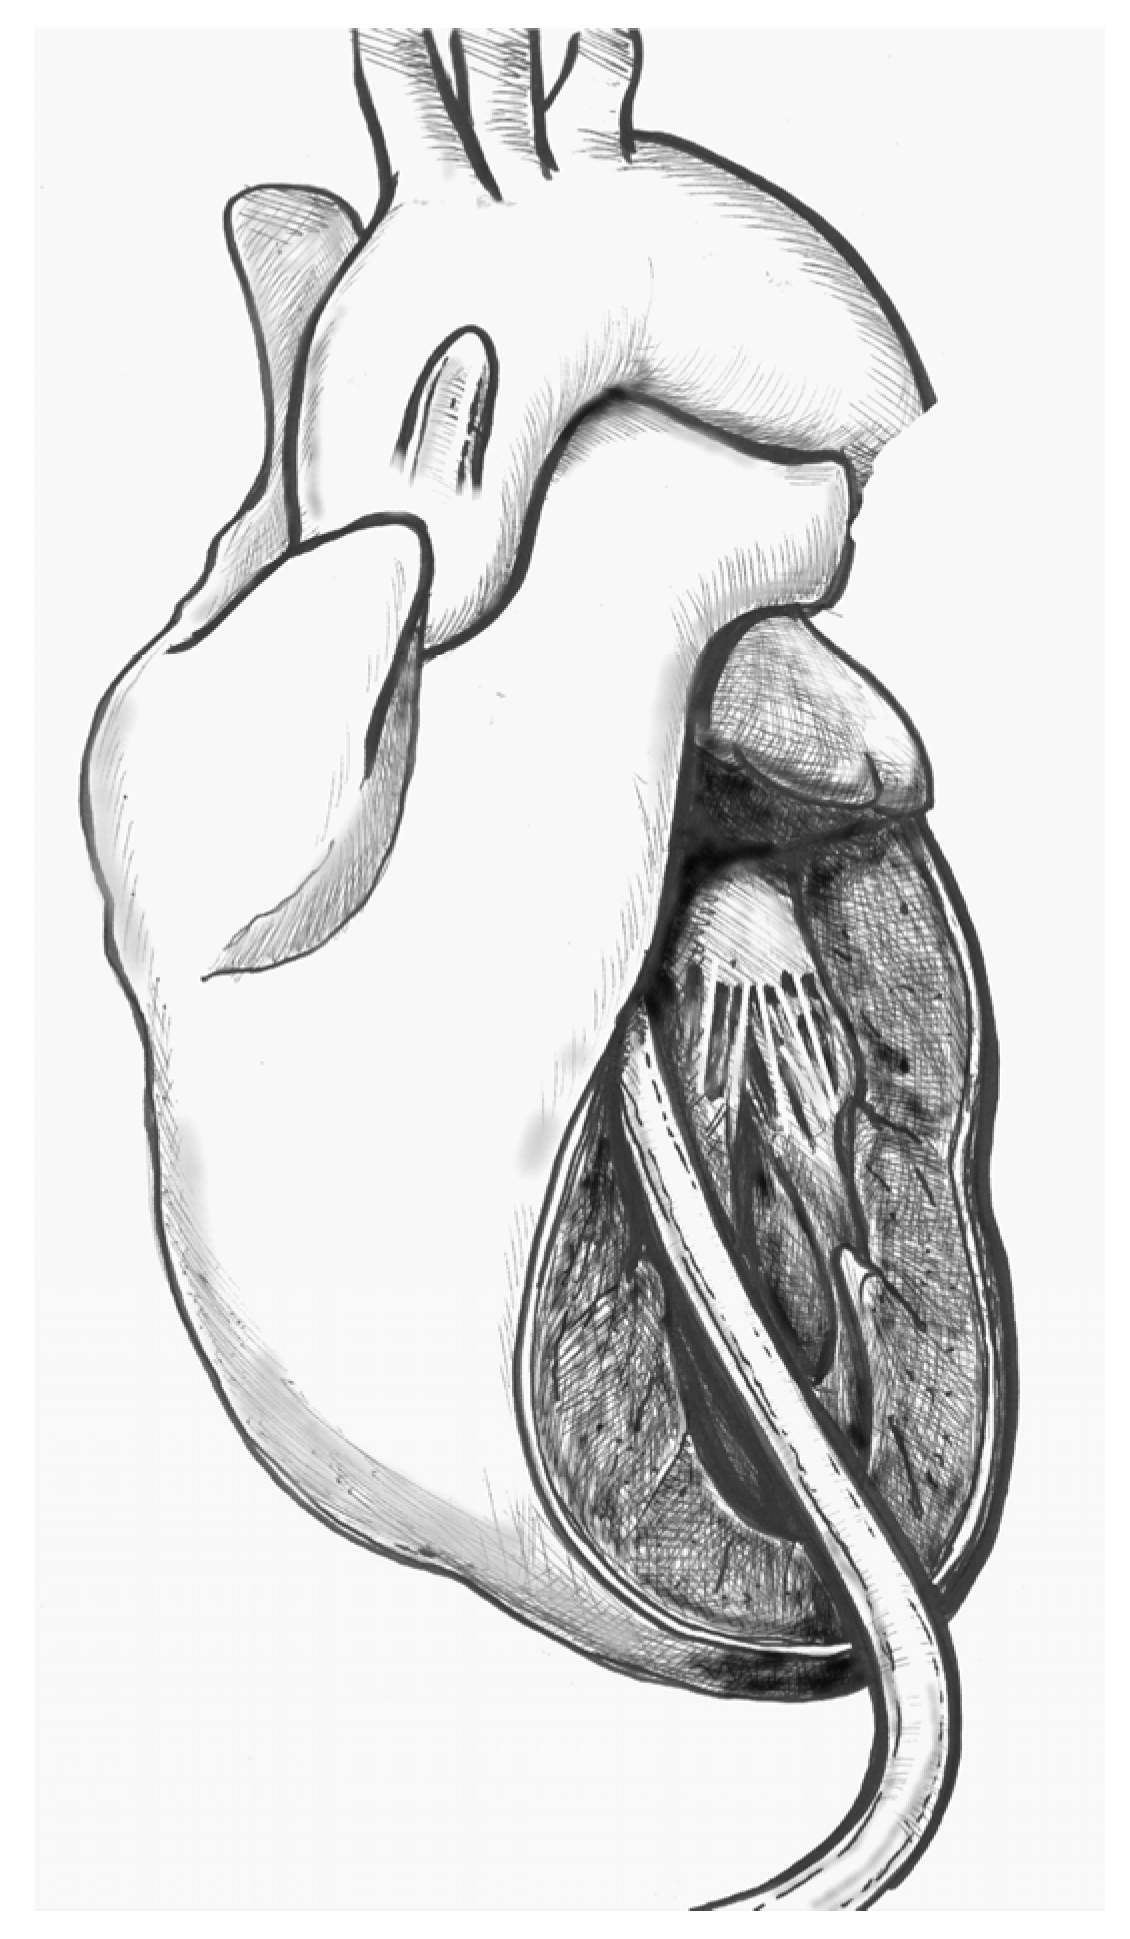

- Figure 4. Ideally, the tip should pass the aortic valve and be positioned in the ascending aorta at the level of the sinus-tubular junction. Confirm this with TEE before starting CPB and reconfirm immediately after the start of perfusion. Avoid “short” positioning in the ventricular cavity, as this is ineffective and potentially dangerous.